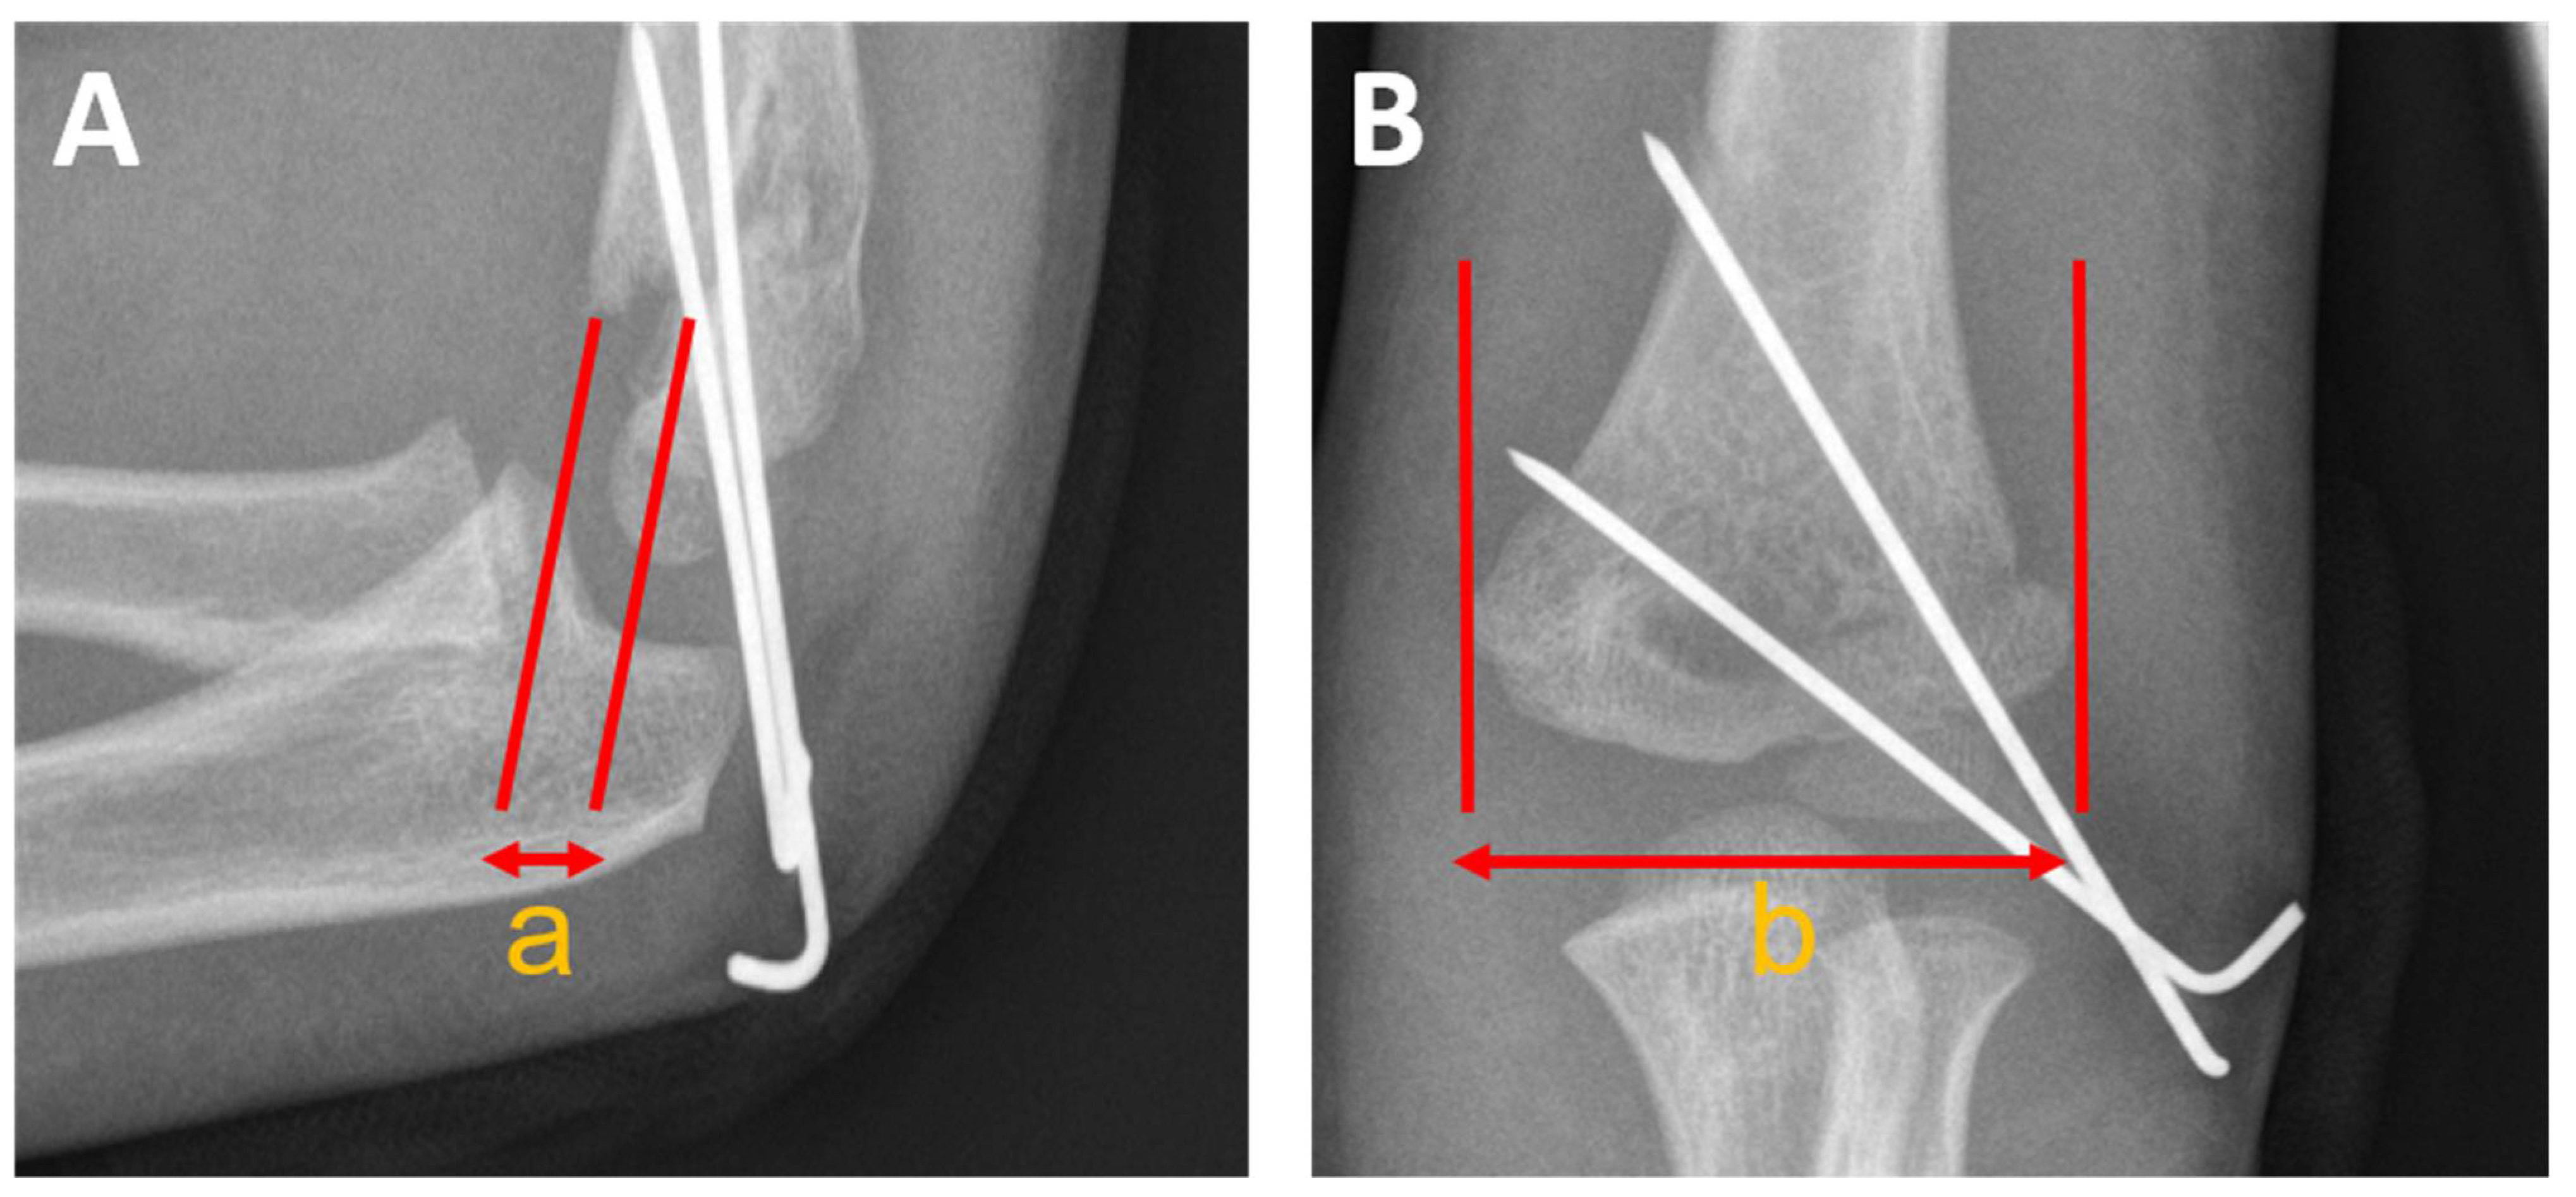

Humeral Ulnar Angle

Baumann’s Angle

Antecurvation Angle

Humeral Trochlear Angle